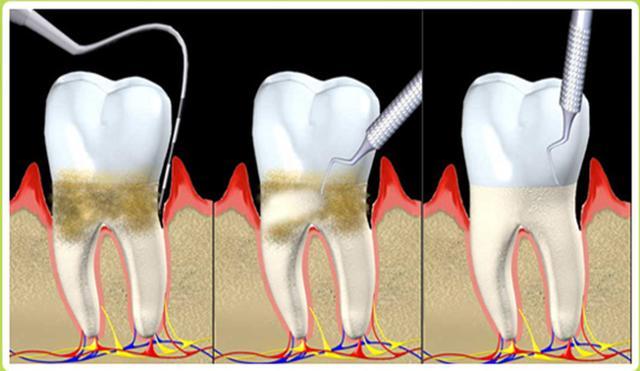

2、导致牙龈出血:牙结石

通俗易懂来说,口腔内的牙菌斑堆积过多,是会形成牙结石的。它通常存在于唾液腺开口处的牙齿表面,刚开始是乳白色的软垢,会逐渐钙化而变硬。肉眼看是呈现黄色、棕色或者黑色。

如果平时不怎么注意口腔卫生,牙结石会越来越容易沉积在牙齿表面,越来越厚的牙结石,刷牙一不注意就会流血。

对于经常牙龈出血的朋友,就要小心了!它有可能是身体内发出的危险信号。有专家研究证实,牙龈反复出血的牙齿比没有出血的牙齿远期脱落的风险高出数十倍。所以定期的口腔清洁很有必要!如果想去除顽固牙菌斑和牙结石,以及大量细菌,建议还是得定期洗牙~